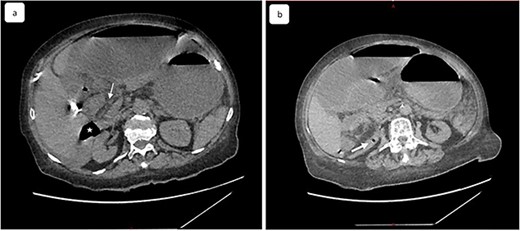

A 65-year-old woman presented to the emergency department with a complaint of acute abdominal pain and distention accompanied by nausea, vomiting and constipation of 2 days. She had a history of diabetes, hypothyroidism, dyslipidemia, mixed connective tissue disease and cholecystectomy. On examination, she had signs of septic shock with a hemodynamic instability, a Glasgow coma scale of 13 with generalized abdominal defense. Initial blood count showed elevated white blood cells (WBC) 22 000 elem/mm3 and C-reactive protein (CRP) of 500 mg/l and procalcitonin of 96 ng/ml. Her lactate on venous blood gas sampling doubled within an hour from 1.64 to 2.3 mmol/l. An urgent abdominal computed tomography (CT) was performed and revealed a dilated loop of bowel within the left upper quadrant and the lesser sac through the foramen of Winslow (Fig. 1). Furthermore, peritoneal fluid and some air bubbles related to intestinal perforation were observed in the omental bursa (Fig. 2). There was also mass effect on the hepatic hilum anteriorly and the inferior vena cava posteriorly. The stomach was pushed back antero-laterally with stretched mesenteric vessels directed to a central point (Fig. 3).

(a) Coronal view of computed tomography of abdomen and pelvis shows the dilated cecal pole and the stomach displaced anteriorly. Peritoneal fluid and some air bubbles related to intestinal perforation were observed in the lesser sac can also be observed (arrow head). (b) Closed-loop small bowel obstruction. CT scan shows a radial array of distented small bowel loops (asterisk) with stretched and thickened mesenteric vessels converging to a central point and anterior to inferior vena cava, which is compressed (white arrow).